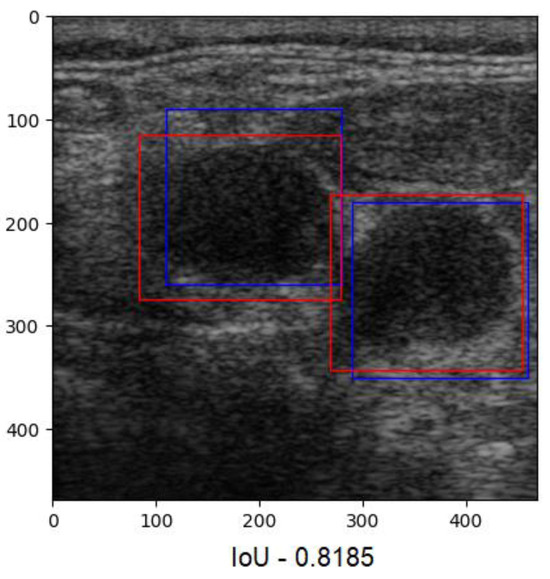

Since our goal was to determine the overlap ratio between the predictions and the labels made by the experts in the field, we searched for alternative ways of reaching our objective, so we applied another metric, IoU. The formula used to calculate IoU is presented in Equation (4) [23]. The better the alignment between the predictions and the label, the more accurate the network. Since this technique verifies each label individually, we averaged the results into a boxplot (Figure 9). The overlap ratio between the predictions and labels ranged between 47% and 84% on the test images, with an average of 74%. Few aberrant labels were ignored. One of the final predictions can be seen in Figure 10.

In our second attempt, we rebuilt the CNN using the sliding window technique. The sliding window technique involves moving a fixed or variable-size window through a data structure (an image, in our case) to efficiently solve problems involving continuous subsets of elements. This method efficiently identifies specific criteria present in data [35]. The images were pre-processed by normalizing the pixels’ values between 0 and 1. With this new technique, new challenges arose because of prediction overlap, which prevented us from correctly calculating the IoU between labels and predictions (Figure 11).

Figure 10. Predictions with an IoU overlap of 81%.

Figure 11. Desaturated image with overlapping labels. Red squares: labels. Blue squares: predictions.